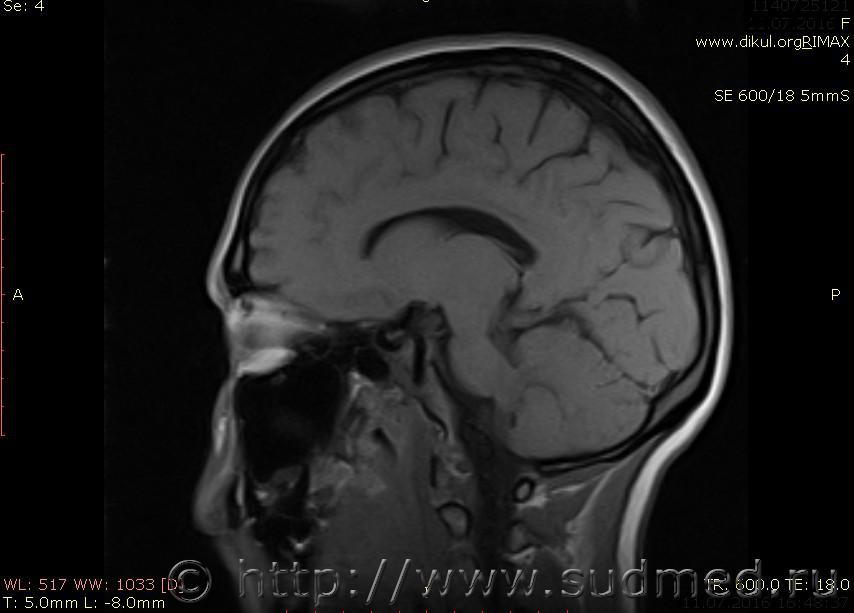

МРТ головного мозга показало: МР-данных за наличие очаговых изменений в веществе головного мозга на момент исследования не выявлено. МР-признаки нарушения соотношения в атланто-осевом суставе. Определяется ассиметрия положения зубовидного отростка С2 относительно боковых масс С1(справа 6,5; слева 4 мм.)

МР-признаки нарушения соотношения в атланто-осевом суставе. Определяется ассиметрия положения зубовидного отростка С2 относительно боковых масс С1(справа 6,5; слева 4 мм.)

Сама по себе эта информация даёт основания подозревать вывих первого шейного позвонка, но однозначно не свидетельствует о наличии вывиха. Нужно смотреть на снимках наличие реакции со стороны мягких тканей, в т.ч. связочного аппарата, нужно анализировать особенности неврологической патологии, её динамику и проч.

Посмотрите пожалуйста снимки, надеюсь на них видны позвонки С1,С2?

Прошу прощения, попробую снова прикрепить файлы. Данные учреждения и пациента убраны.